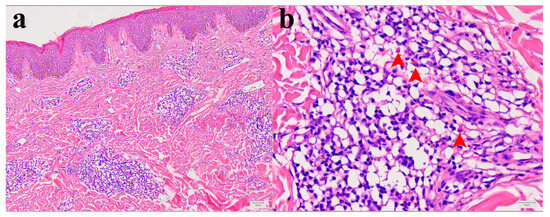

2.6. Histological Findings in Skin Biopsy of Patient I

Histopathological analysis showed mild epidermal hyperkeratosis, dermal edema, and a moderately dense, chronic inflammatory infiltrate, containing some eosinophilic granulocytes, unevenly distributed but mainly perivascular oriented, throughout the thickness of the involved dermis and at the border with subcutaneous fatty tissue. The capillary blood vessels were dilated. The findings corresponded to chronic superficial and deep perivascular lymphocytic infiltrate with eosinophils and minimal or no epidermal alteration. Such rather nonspecific tissue reactions can be seen in a various skin reactions such as in a dermal hypersensitivity reaction/response and in a urticarial hypersensitivity reaction (Figure 2a,b).

Figure 2.

Morphology of Patient I skin lesion biopsy. (a) Skin biopsy with mild epidermal hyperkeratosis, dermal edema, and chronic, moderate, perivascular, and inflammatory infiltrate. Capillary blood vessels are slightly dilated (hematoxylin and eosin (H&E), X100). (b) Higher magnification of inflammatory infiltrate with few eosinophilic granulocytes (red arrowheads) within dominant lymphocytic infiltrate (H&E, X400).

The histopathological changes observed in Patient I were crucial for establishing the final diagnosis, as other laboratory parameters yielded unremarkable results. Changes in the skin biopsy were comparable, or even equivalent, to those observed in clinically manifested papular dermatitis or urticaria, terms often used synonymously with arthropod bite reactions and drug-induced hypersensitivity syndrome [12]. Lesion morphology is suggestive of chronic processes and it is not equivalent to findings in a skin biopsy after tick removal, where eosinophils are the most dominant leukocyte population [13]. On the other hand, similar skin changes were found more than 25 years ago in two lumbermen from France who reported to a clinic due to persistent skin reactions following tick bites [14].